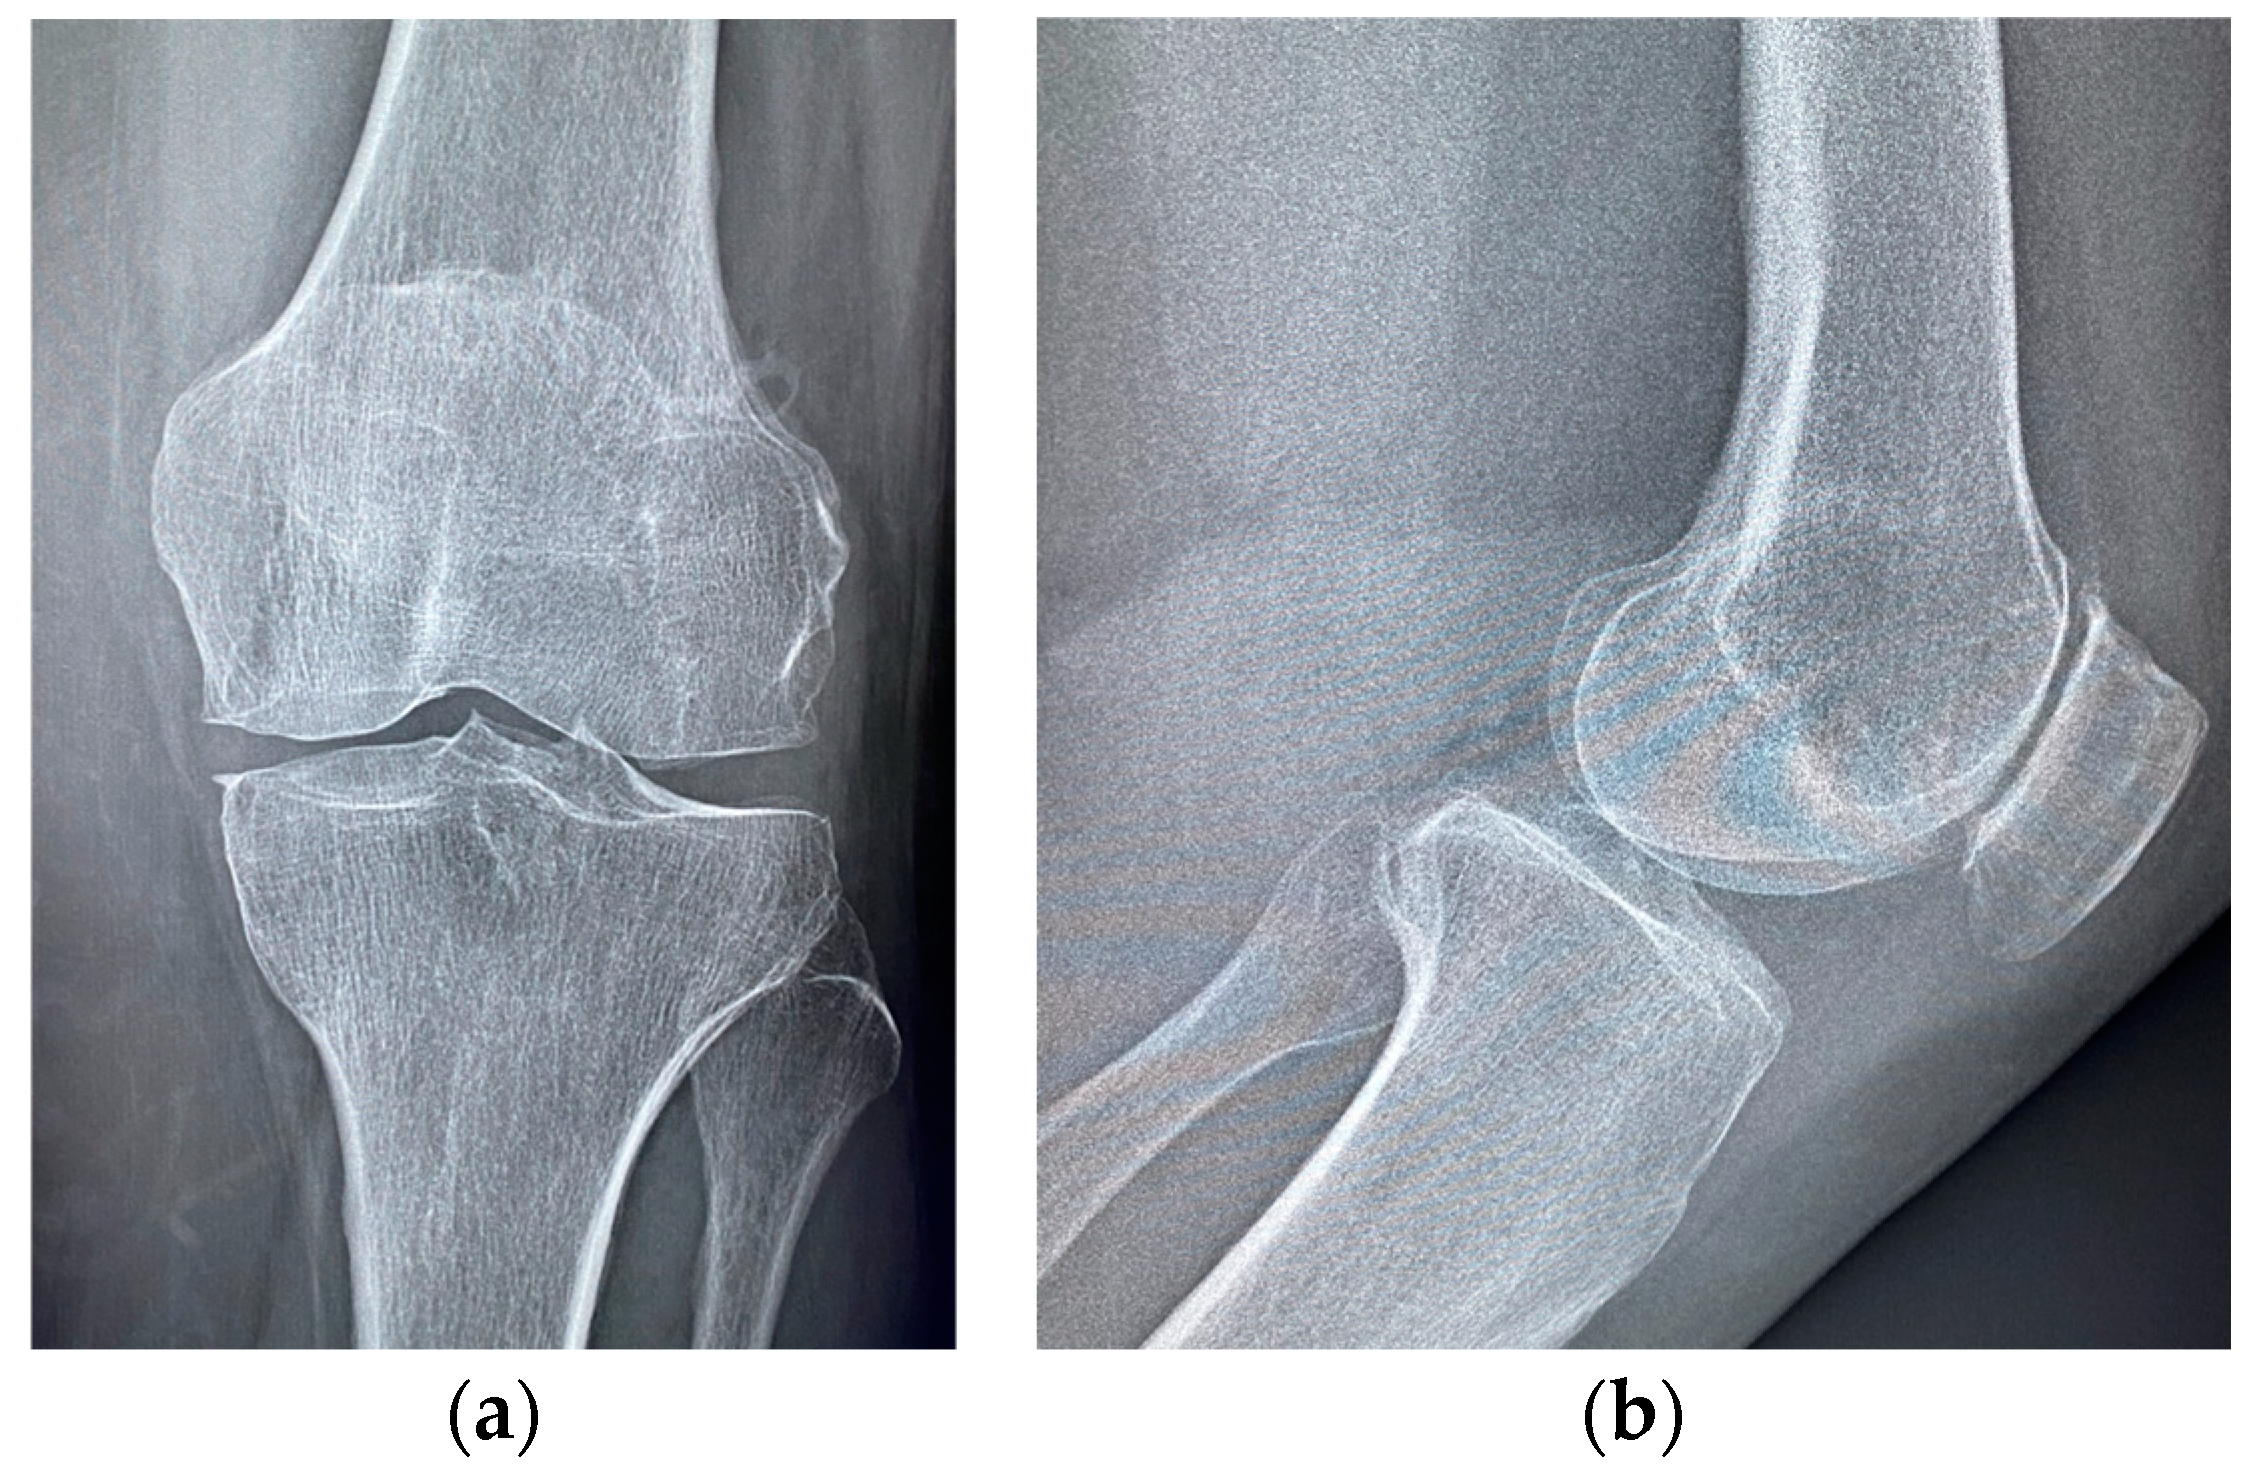

| Stage I | Opacity of fluid, redness of the synovial membrane, possible petechial bleeding, no radiological alterations |

| Stage II | Severe inflammation, fibrinous deposition, pus, no radiological alterations |

| Stage III | Thickening of the synovial membrane, compartment formation (“sponge-like” arthroscopic view, especially in the suprapatellar pouch), no radiological alterations |

| Stage IV | Aggressive pannus with infiltration of the cartilage, possibly undermining the cartilage, radiological signs of subchondral osteolysis, possible osseous erosions and cysts |